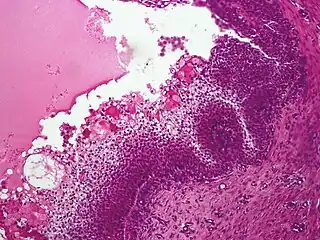

Micrograph showing an acrospiroma. H&E stain.

Hidradenoma refers to a benign adnexal tumor of the apical sweat gland.[1][2] These are 1–3 cm translucent blue cystic nodules. It usually presents as a single, small skin-colored lesion, and may be considered closely related to or a variant of poromas.[3] Hidradenomas are often sub-classified based on subtle histologic differences, for example:[4]